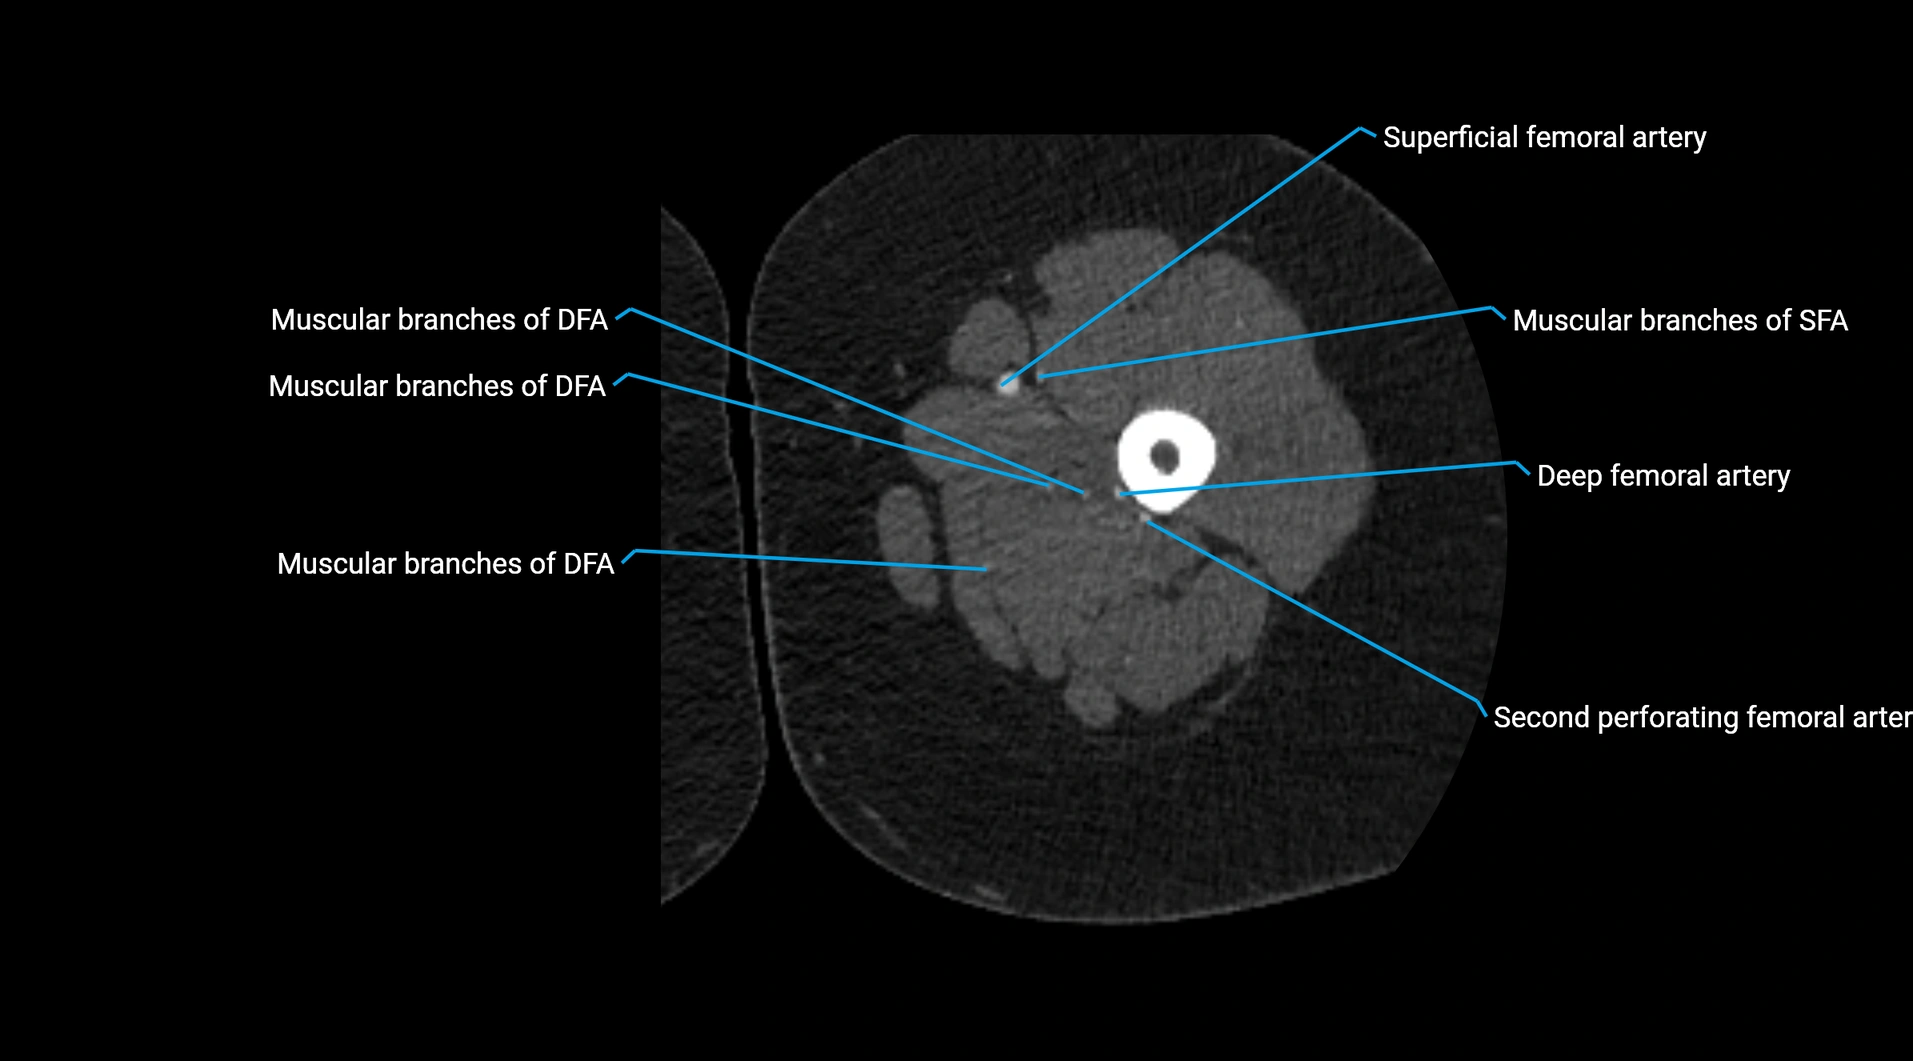

Contrast-enhanced CT (CTA):

• Gold standard for abdominal aortic imaging

• Provides excellent detail of lumen, wall, aneurysm, thrombus, and branch vessels

• Multiplanar and 3D reconstructions help in aneurysm measurement, stent graft planning, and dissection evaluation

• Detects acute rupture, traumatic injury, or occlusion with high sensitivity